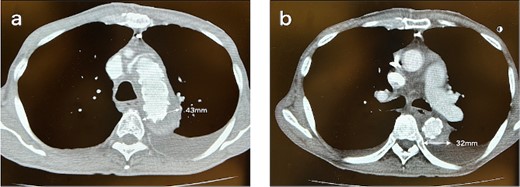

A 62-year-old male presented at the previous hospital with left hemiplegia. Computed tomography (CT) detected an aortic dissection with malperfusion of the right brachiocephalic artery, necessitating a referral to our institution. Preoperative CT showed the primary entry tear in the distal aortic arch and a patent false lumen. A total arch replacement was successfully performed using the fenestrated FET technique. The surgical procedure involved median sternotomy, establishment of extracorporeal circulation with right atrial drainage and perfusion via right axillary artery, circulatory arrest at 28°C and selective cerebral perfusion to perfuse all cervical vessels. Myocardial protection was provided by retrograde cardioplegia. Following resection of the aorta at zone 1, FET was inserted and deployed into the aorta, perfusing blood from the femoral artery. Fenestration of the graft at the ostium of the second and third cervical branches was performed. A U-shaped graft was placed around cervical branches, and three 4-0 polypropylene U-shaped sutures were roughly placed to fix the open stent graft, leaving some gaps between the sutures. Subsequent procedures included anastomosis of a four-branch graft to the distal aorta, reconstruction of the brachiocephalic artery and proximal anastomosis. Postoperative contrast-enhanced CT on day 5 showed no endoleak and favorable remodeling of the descending aorta (Fig. 1). However, after 6 months, follow-up CT detected a fenestration-related endoleak and an enlarged aortic arch (Fig. 2), prompting reoperation. The reoperation involved median re-sternotomy, establishment of extracorporeal circulation with right femoral vein drainage and perfusion via an 8-mm graft anastomosed to the left axillary artery, circulatory arrest at 28°C, and selective cerebral perfusion to perfuse all cervical vessels. Upon opening the artificial graft, it was observed that the stent graft had some gap between fixed U-sutures and had become detached from the aorta, revealing a small entry adjacent to it, which communicated with the false lumen. The left subclavian artery (LSCA) was ligated, and the left common carotid artery was transected at its origin and sutured. An open stent was inserted distally, followed by placement of a felt strip and a 4-0 running suture. Subsequent procedures included anastomosis of a four-branch graft to the distal aorta, reconstruction of the three cervical branches and proximal anastomosis. The surgery was completed without complications. Postoperative contrast-enhanced CT on day 5 revealed resolution of the endoleak with no blood flow into the false lumen of the arch. Follow-up CT 3 months after discharge revealed favorable remodeling of the aortic arch (Fig. 3).

CT 6 months after the initial surgery reveals an endoleak from the fenestration (indicated by the white arrow), antegrade flow in the false lumen, and an enlarged aorta at the levels of the aortic arch (a) and the carina of the trachea (b). Sagittal image (c). An illustrative diagram (d) shows the schema of endoleak from fenestration (indicated by the black arrow).